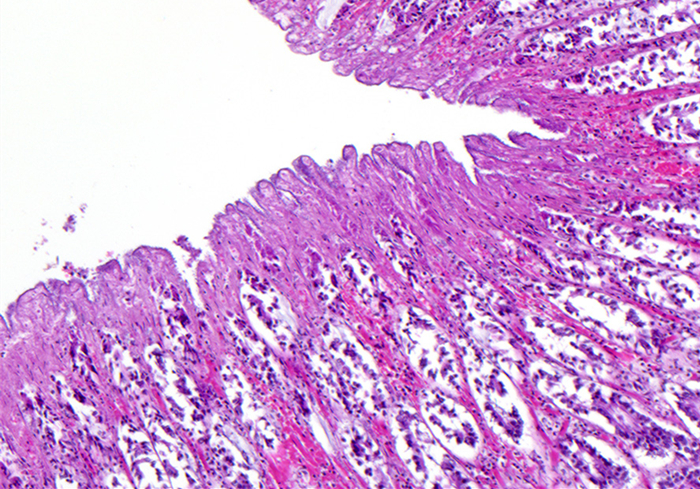

而蛋白丢失性肠病就是指血浆蛋白经肠道黏膜时出现向肠腔内大量排出,并随着粪便一起丢失的一种病症。如果狗狗出现了蛋白丢失性肠病,最终的结果就会导致血浆蛋白的浓度降低,出现低蛋白血症,严重的情况下会威胁生命。

7.肠道炎症性疾病

肠道炎症性疾病是一种统称,主要可以分为克罗恩病和溃疡性结肠炎两个类型。

肠炎作为铲屎官经常要打交道的一类疾病,它的外在表现特征也是广为人知的,比如呕吐、腹泻、血便、体重减轻等症状。